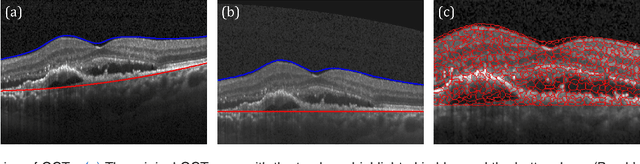

Abstract:The identification and quantification of markers in medical images is critical for diagnosis, prognosis, and disease management. Supervised machine learning enables the detection and exploitation of findings that are known a priori after annotation of training examples by experts. However, supervision does not scale well, due to the amount of necessary training examples, and the limitation of the marker vocabulary to known entities. In this proof-of-concept study, we propose unsupervised identification of anomalies as candidates for markers in retinal Optical Coherence Tomography (OCT) imaging data without a constraint to a priori definitions. We identify and categorize marker candidates occurring frequently in the data, and demonstrate that these markers show predictive value in the task of detecting disease. A careful qualitative analysis of the identified data driven markers reveals how their quantifiable occurrence aligns with our current understanding of disease course, in early- and late age-related macular degeneration (AMD) patients. A multi-scale deep denoising autoencoder is trained on healthy images, and a one-class support vector machine identifies anomalies in new data. Clustering in the anomalies identifies stable categories. Using these markers to classify healthy-, early AMD- and late AMD cases yields an accuracy of 81.40%. In a second binary classification experiment on a publicly available data set (healthy vs. intermediate AMD) the model achieves an area under the ROC curve of 0.944.

Abstract:The identification and quantification of markers in medical images is critical for diagnosis, prognosis and management of patients in clinical practice. Supervised- or weakly supervised training enables the detection of findings that are known a priori. It does not scale well, and a priori definition limits the vocabulary of markers to known entities reducing the accuracy of diagnosis and prognosis. Here, we propose the identification of anomalies in large-scale medical imaging data using healthy examples as a reference. We detect and categorize candidates for anomaly findings untypical for the observed data. A deep convolutional autoencoder is trained on healthy retinal images. The learned model generates a new feature representation, and the distribution of healthy retinal patches is estimated by a one-class support vector machine. Results demonstrate that we can identify pathologic regions in images without using expert annotations. A subsequent clustering categorizes findings into clinically meaningful classes. In addition the learned features outperform standard embedding approaches in a classification task.